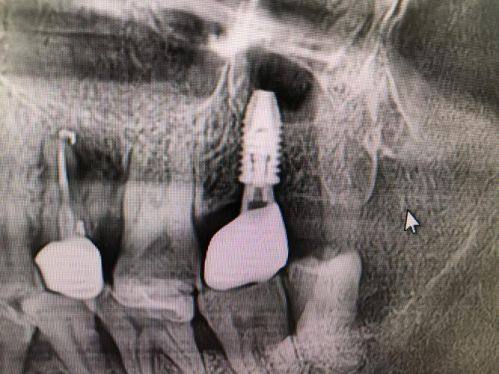

高难度骨劈开同期种植:可处理骨宽度仅3mm的复杂病例,同期完成骨劈开与种植体植入,无需二次植骨等待。

李先生:高难度骨劈开种植

"我的后牙区骨宽度只有3mm,特别多医院都说要先植骨等半年才能种,后来找到昆明市口腔医院种植科的肖旭辉医生。他给我做了骨劈开同期种植,不用等待植骨的时间,大大缩短了治疗周期。手术特别顺利,术后修复得也快,现在牙齿用着特别稳,吃东西完全没问题,真的特别感谢医生的不错技术,解决了我的大难题。"